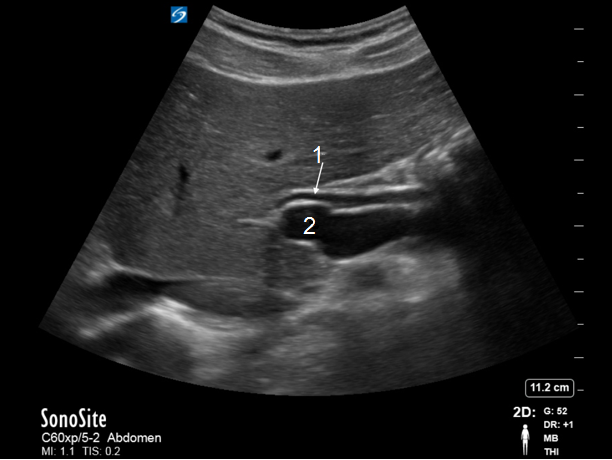

Bild: Gallenblase, Ductus choledochus (DC) – lange Achse

Ductus choledochus (DC)

Hauptpfortader